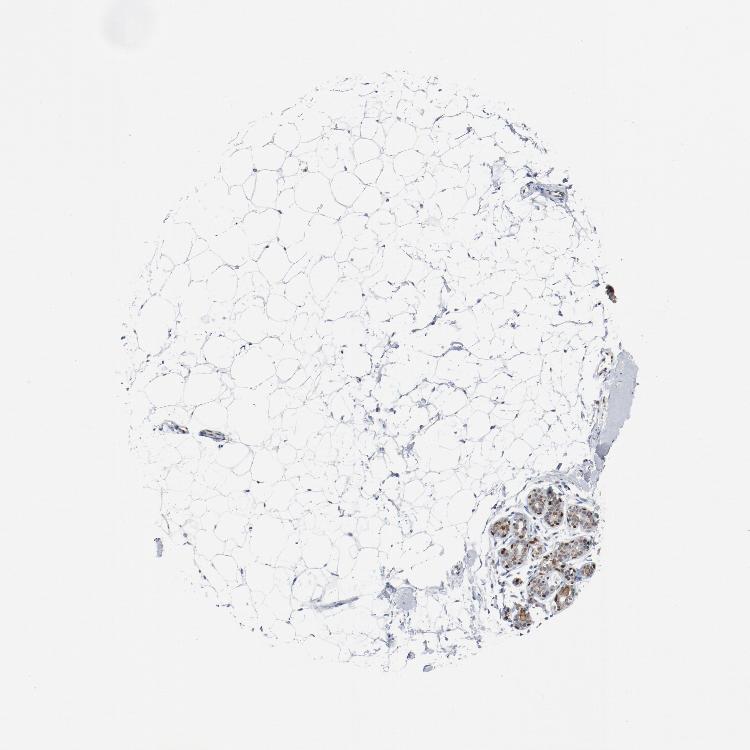

BREAST - Antibody stainingi

Antibody staining in the annotated cell types in the current human tissue is reported as not detected, low, medium, or high, based on conventional immunohistochemistry profiling in selected tissues. This score is based on the combination of the staining intensity and fraction of stained cells.

Each image is clickable and will lead to virtual microscopy that enables deeper exploration of all samples and also displays staining intensity scores, fraction scores and subcellular localization as well as patient and tissue information for each sample.

Antibody HPA003876Antibody CAB011501

Adipocytes Not detectedLow

Glandular cells HighHigh

Myoepithelial cells MediumMedium